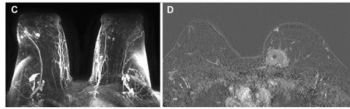

In addition to a lower rate of preoperative breast MRI use, emerging research found that Black women with breast cancer who didn’t have a preoperative MRI had a higher positive surgical margin rate than White women with no preoperative MRI.